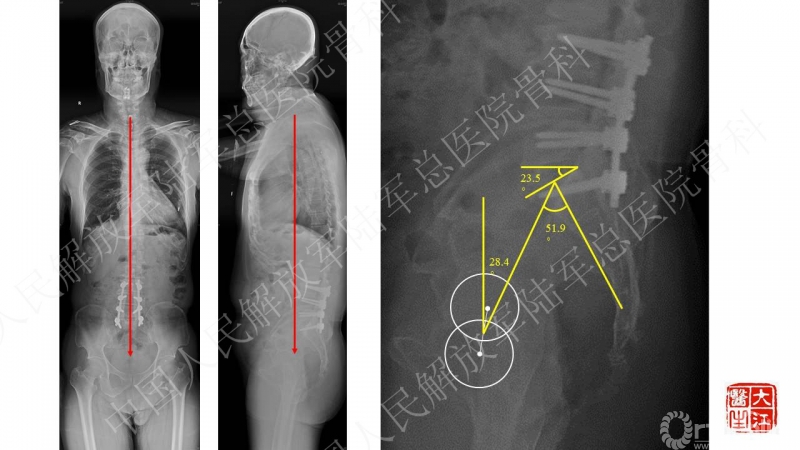

患者主诉为腰痛伴下肢疼痛,腰痛为主,翻身活动、下地时疼痛加重。体格检查也为下腰段的叩压痛,影像可见腰5-骶1断棒。断棒的原因都是力学应力相关的原因,而患者SVA(矢状位垂直轴)不大,全身平衡状态尚可。结合CT表现,应怀疑腰5-骶1节段未融合。

本病例的焦点在患者腰痛的原因,患者明确其腰痛非慢性腰痛,伤后出现。结合病史、体格检查、断棒的表现,主要考虑下腰段的原因。要考虑两个原因,一是腰5-骶1的未融合,断棒后不稳,局部应力集中。二是断棒后局部异常活动,带动瘢痕牵拉硬膜囊及神经根的向背侧牵拉,这种异常活动在残留小关节的抵挡下会引起严重卡压,而出现下肢的疼痛、甚至神经功能损害等。患者行原术区内固定取出,腰5-骶1内固定术,术后取得良好效果,证实患者本次疼痛病因为腰5-骶1节段断棒后应力集中、异常活动。

患者疼痛为伤后出现,不是根性痛表现,而是机械性疼痛,活动及下地时明确。上位节段已融合,考虑到长节段固定后腰5-骶1节段由于杠杆原理出现内固定失败的风险大,术中取出原内固定后,仅行腰5-骶1短节段固定,取得了良好的临床效果。美中不足的是,因椎管内瘢痕粘连重,未重新加强融合,之后需严密随访。